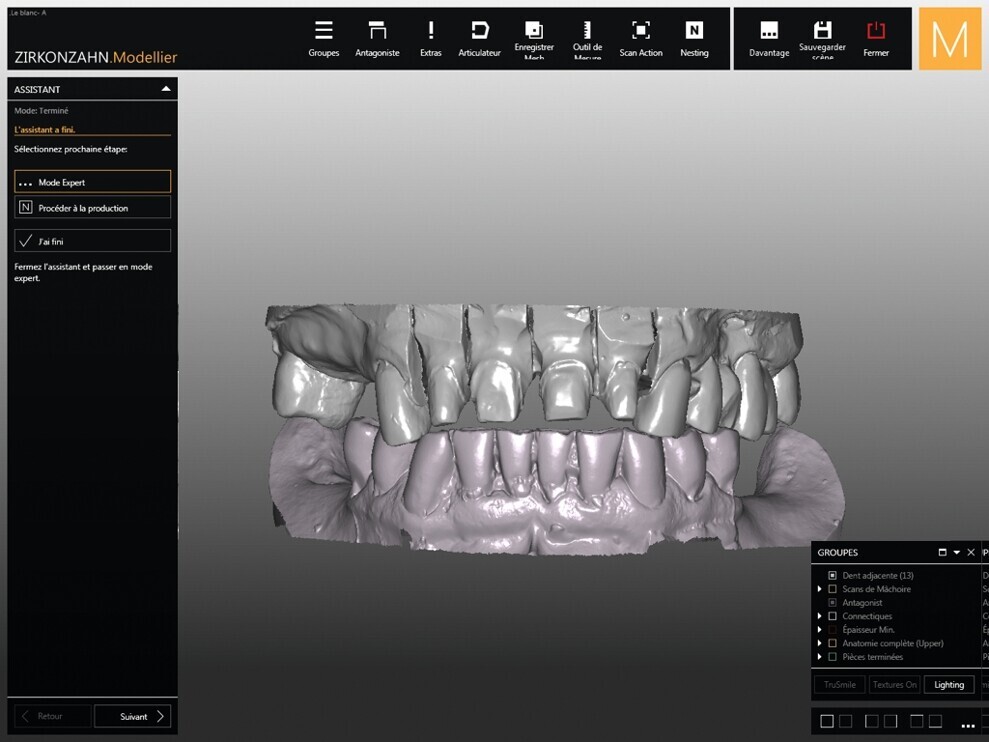

Quatre jours plus tôt, la figure 6 montre le wax-up numérique (logiciel Zirkonzahn.Modellier, Zirkonzahn). Pour le prothésiste dentaire, la difficulté principale a été de repenser l’anatomie des incisives maxillaires, tout en réhabilitant la forme initiale des dents. La forme globale des autres dents donne un aperçu de la typologie géométrique des dents : rondes, carrées, triangulaires. Toutes les formes sont possibles mais une seule forme est adaptée à ce cas clinique. Le logiciel de CAD/CAM permet un guidage automatique, pour obtenir uniforme harmonieuse. Puis le technicien de laboratoire va reprendre la main et procéder individuellement, afin d’apporter des touches humaines à un système informatique.

Fig. 7 : Modèle numérique de l’arcade supérieure et l’arcade inférieure.

Cinq jours plus tôt, la figure 7 montre le modèle virtuel après l’étape de scan numérique (logiciel Zirkonzahn. Scan). Le logiciel va permettre de numériser des modèles physiques pour les importer dans la suite logicielle. Les modèles numériques sont alors montés en occlusion avec un articulateur virtuel. Les limites de préparation sont tracées, et grâce au détourage préalable, chaque dent préparée peut être individualisée, pour passer à l’étape suivante de modélisation de la couronne.